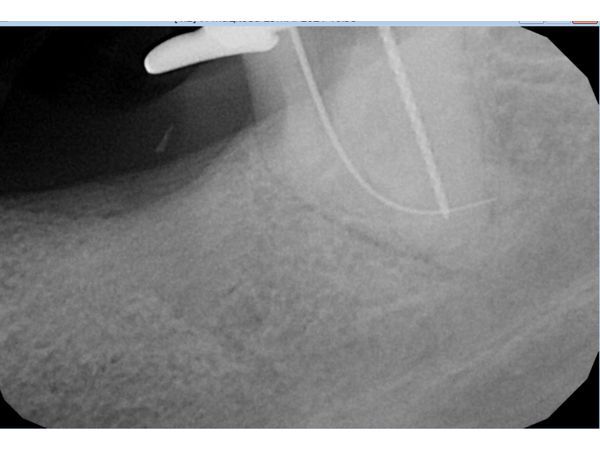

В итоге после первого посещения пациентке полностью восстановили анатомию каналов и расширили их верхушки в соответствии со стандартами лечения (дистальный — до 60-го размера 2-й конусности, медиальные — до 35-го размера 4-й конусности). В каналах оставили смесь гидроксида кальция сроком на 7–14 дней.